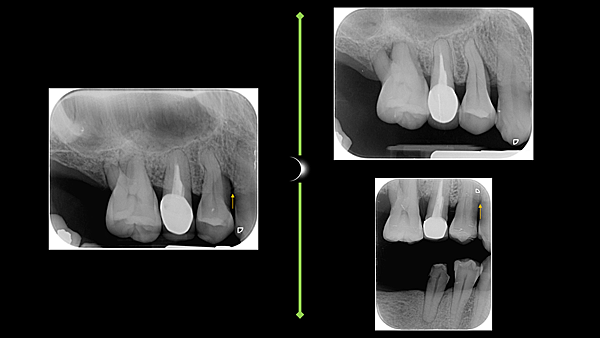

牙周囊袋深度降低到4mm以下

骨質密度增加

美觀的部分則為最少的牙齦萎縮,甚至像這個病例整體癒合非常良好,帶動了牙齦向上爬升

而如此完美的結果,莊醫師是以不開刀也不補骨的方式達成,在顯微鏡下以雷射與其他精細的工具進行牙齦下根面清創